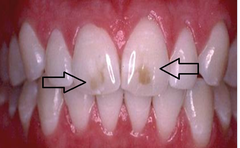

Turner's tooth

Front

Hypocalcified permanent tooth

Back